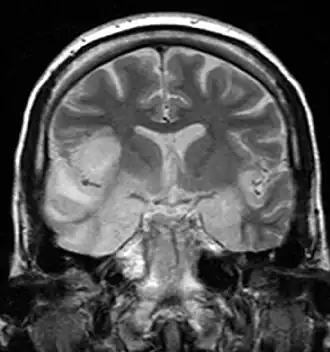

| Ressonância magnética de paciente com encefalite por vírus do herpes simples em que se observa alto sinal nos lobos temporais e no giro frontal inferior | |

Hemorragia também é incomum, porém encontrada nas encefalites por Herpes e por amebas. Ressonância magnética oferece melhor resolução, mas o diagnóstico é clínico: paciente com febre, vômitos, alteração da consciência ou do comportamento devem ser investigados para encefalites sem perda de tempo. Em pacientes com encefalite por herpes simples, o eletrencefalógrafo pode mostrar ondas afiadas em um ou ambos os lóbulos temporais.